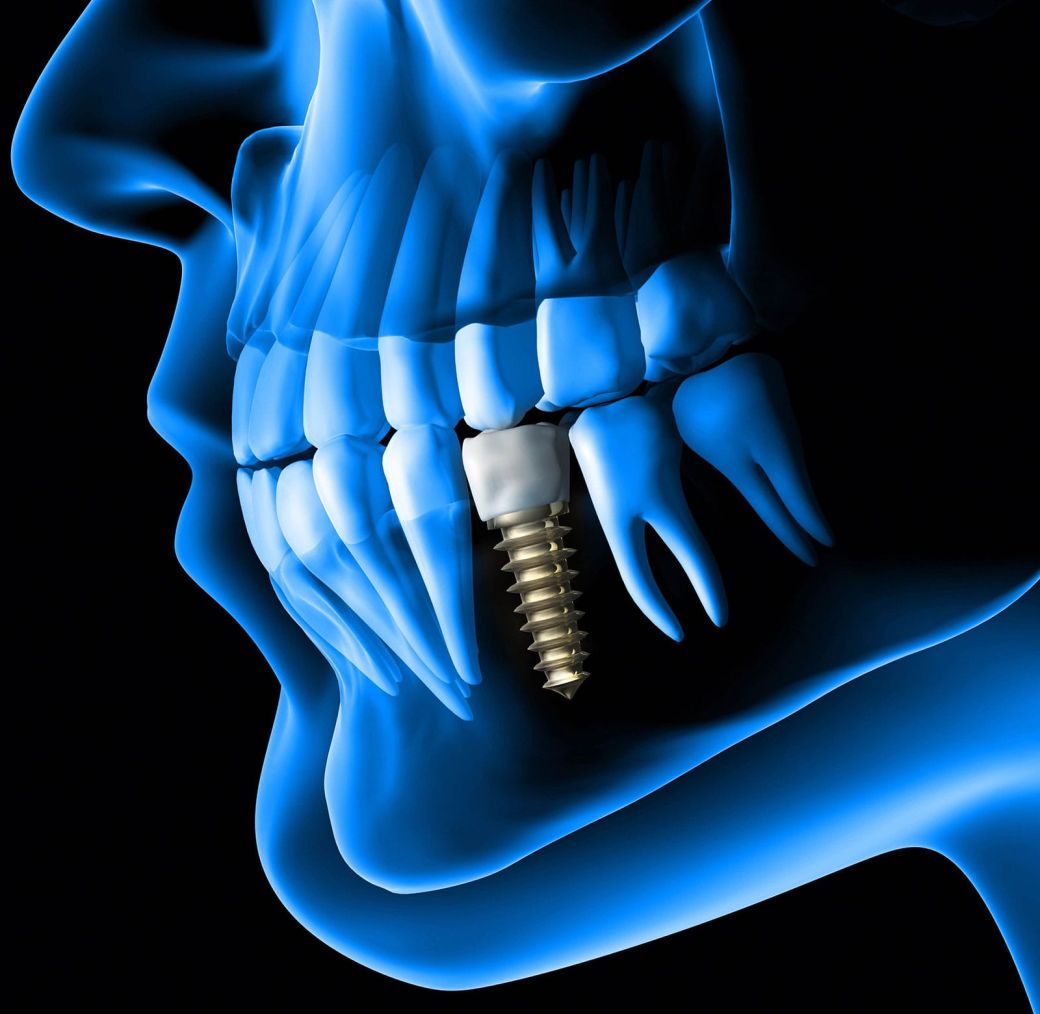

L’implantologie est une des disciplines de la Chirurgie Dentaire qui traite du remplacement d’une racine dentaire par une racine artificielle en titane placée dans l’os maxillaire ou mandibulaire.

Cette racine artificielle ou implant dentaire est destinée à accueillir une prothèse dentaire.

L’IMPLANT T3®, LE CHOIX DE LA QUALITE

Notre cabinet a choisi depuis plusieurs années de poser un implant de qualité, l’implant T3 distribué par ZIMMER BIOMET.

Cet implant a été spécialement conçu pour offrir des résultats esthétiques grâce à la préservation des tissus.